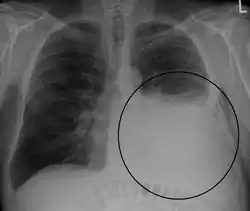

Massive left-sided pleural effusion (whiteness) in a patient presenting with lung cancer. -

Massive pleural effusion, later proven to be hemothorax in a South Indian male.